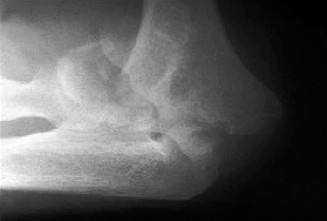

Treat a patient with infected total shoulder arthroplasty? CASE 21 A 70-year-old, right-hand-dominant female presents to clinic complaining of 4 years of gradually worsening chronic right shoulder pain and stiffness. She says the pain is worse at night and with any range of motion, denies a history of trauma, pain in other extremities, or numbness or tingling of the right upper extremity. She notes that her mother suffered from rheumatoid arthritis that affected her shoulder. Physical examination reveals decreased muscle bulk over the right supra- and infraspinatus fossae compared to the contralateral side, limited active and passive ROM, marked weakness with external rotation, and 4+/5 strength with shoulder abduction. X-rays of the right shoulder are shown in Figures 2–58 and 2–59.

Figure 2–58

Figure 2–59

The correct answer is (C). Rotator cuff tear arthropathy consists of a combination of rotator cuff insufficiency, glenohumeral joint degenerative changes, and superior humeral head migration. It is more common in women and also more often found on the dominant side. The patient’s clinical examination with weakened external

rotation and muscle atrophy signaling incompetent supra- and infraspinatus muscles point to rotator cuff insufficiency, and her plain films reveal narrowed glenohumeral joint space as well as superior migration of the humeral head. Choice D is incorrect because, while radiographs would show narrowing of the glenohumeral joint space, they would also likely show numerous osteophytes and posterior wear of the glenoid. Choice B is incorrect because, while adhesive capsulitis does present as decreased active and passive range of motion, the patient’s constellation of symptoms pointing towards rotator cuff insufficiency along with the radiographs make cuff tear arthropathy the more likely choice. Finally, Choice A is incorrect because even though she has a positive family history of rheumatoid arthritis, it is less likely to present only in a single joint. Also, rheumatoid arthritis on radiography appears more as an erosive process without the characteristic superior migration of the humeral head.